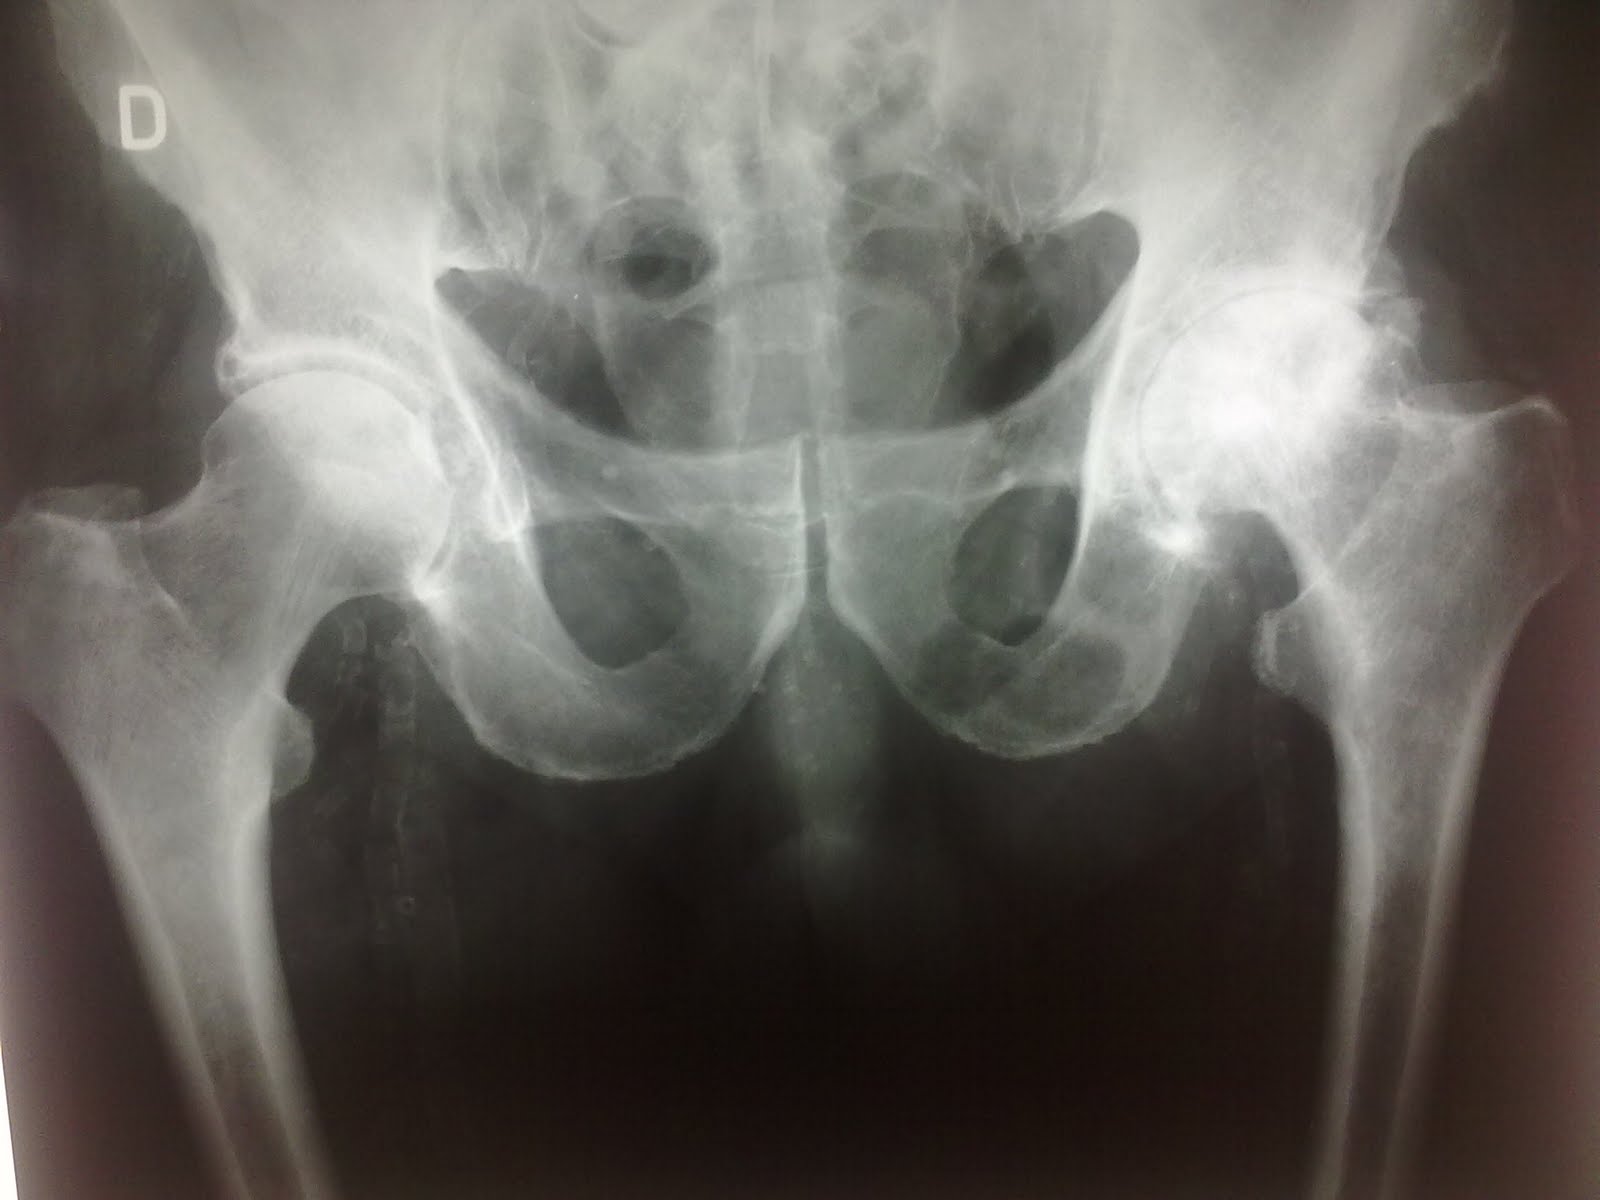

La imagen que pertenece a un varón de 70 años, muestra los cambios radiológicos de artrosis(pinzamiento espacio articular, esclerosis subcondral con aumento de la densidad ósea,quistes subcondrales y osteofitos), leves en la cadera derecha y muy severos en la izquierda.